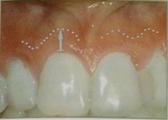

· Ширина кератинизированных тканей (ШКД) – измеряют от десневого края до слизисто-десневой линии (которая определяется тестом «валика» или окрашиванием слизистой растворами йода)(рис. 10).